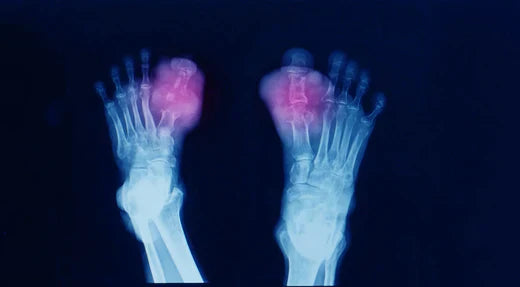

Understanding Tophaceous Gout: Symptoms, Diagno...

Tophaceous gout is an advanced form of gout characterized by the accumulation of uric acid crystals in the soft tissues around the joints, resulting in the formation of tophi, or...